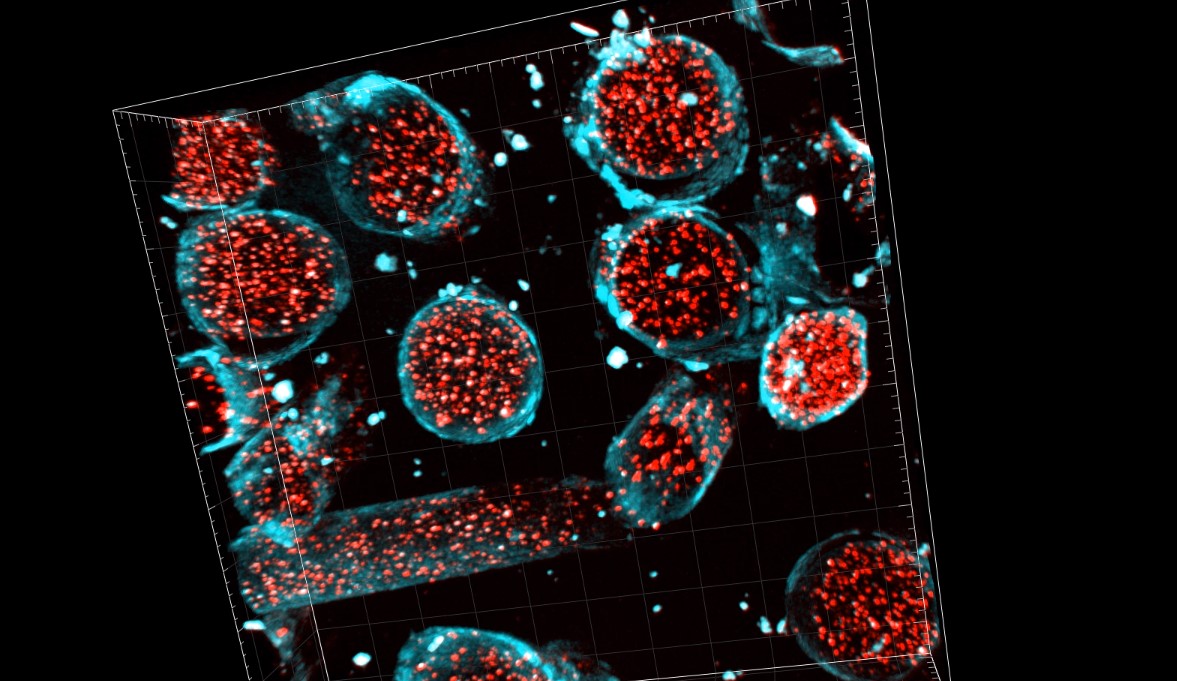

Why Are the LFT Swab Bristles Tube-like and Why Do They Stay in Your Body?

Why do the LFT bristles break away so easily, and why are they tube-like? Prof Anthony Brookes and Dr Kees Straatman have taken a closer look with a laser microscope and sent the images to the Daily Sceptic.